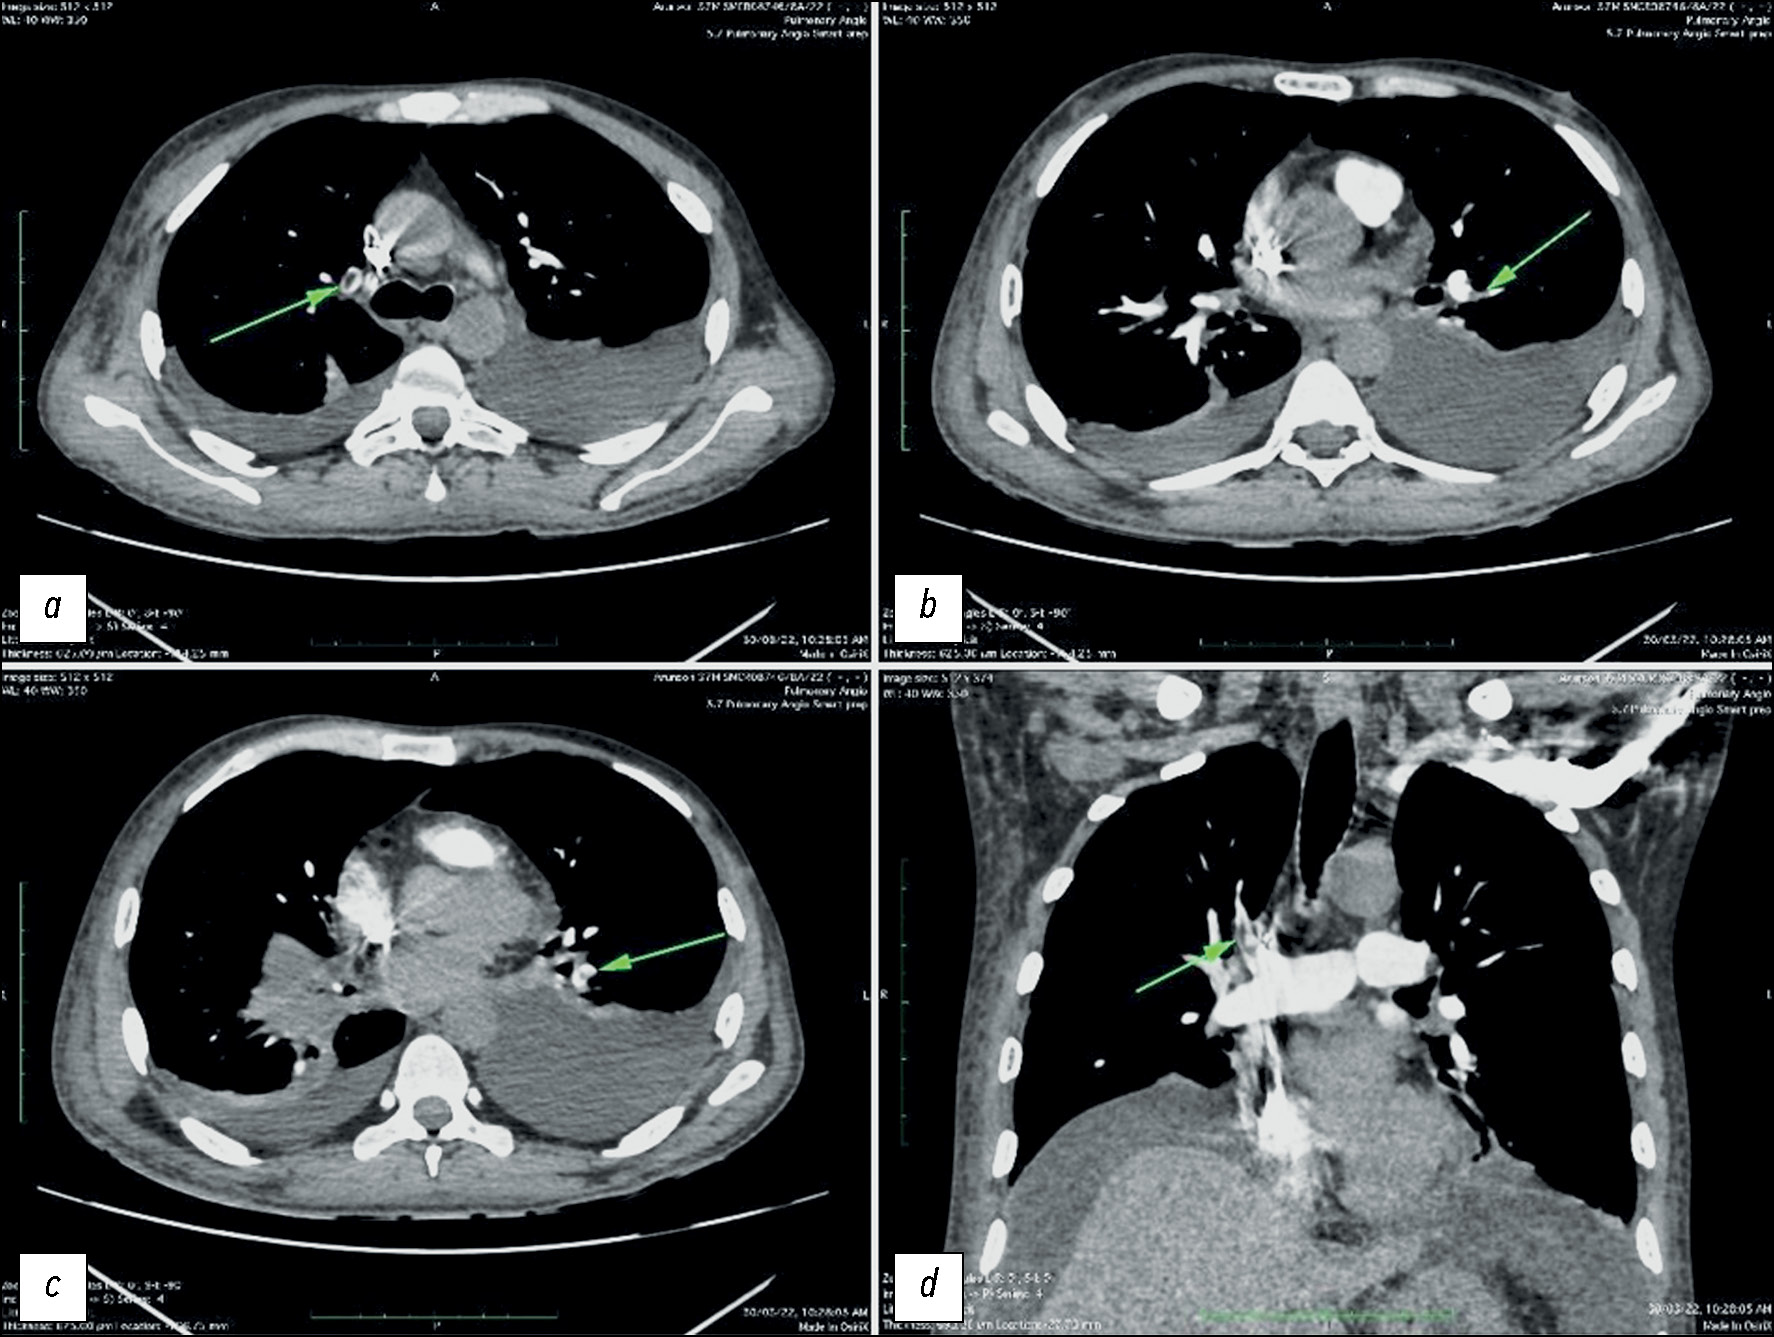

RESULTS: In this study, 11 patients exhibited pulmonary thromboembolism, and 7 showed significant bowel changes such as bowel wall thickening, mesenteric ischemia, and omental infarction, indicative of potential gastrointestinal involvement of patients with COVID-19. A positive correlation was found between pulmonary embolism prevalence in patients with COVID-19. Pulmonary embolism was diagnosed at a mean of 11 days from disease onset. Of the 24 patients with severe acute respiratory illness, 7 showed pulmonary embolism, detected by computed tomography pulmonary angiography. In addition, of the 10 patients on mechanical ventilation, pulmonary embolism was found in 7. Among the seven patients with bowel changes, four had pulmonary embolism, as detected by computed tomography pulmonary angiography, indicating a significant association between the two concomitant complications. The observed bowel changes were attributed to intravascular thrombosis.

CONCLUSIONS: Based on our findings, pulmonary emboli and bowel changes often occur in patients with COVID-19. Multivariate analyses also revealed a connection between invasive mechanical ventilation and pulmonary embolism. The results indicate that patients with severe COVID-19 may also experience concurrent acute pulmonary embolism. Thus, for these patients, the use of contrast-enhanced computed tomography instead of standard non-contrast computed tomography may aid in treatment decision-making.